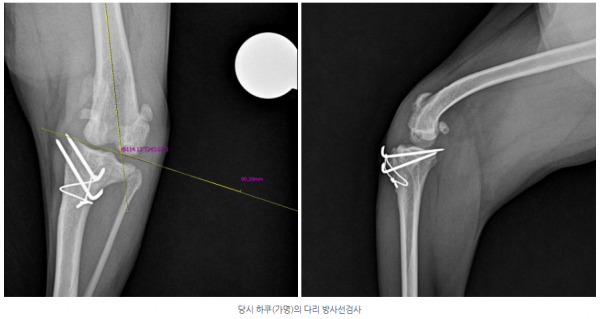

정밀 검사 결과

- 좌측 슬관절에서 슬개골 재탈구

- anatomic lateral distal femoral angle (aLDFA) 약 114°로 확인

- 슬개골 경화 및 주변 골증식체

- 관절 삼출 증가

- 십자인대 단열 소견 확인되지 않음

➡ 이는 단순 통증 문제가 아닌

구조적 문제로 인한 ​슬개골탈구 재수술

적응증에 해당하였습니다.